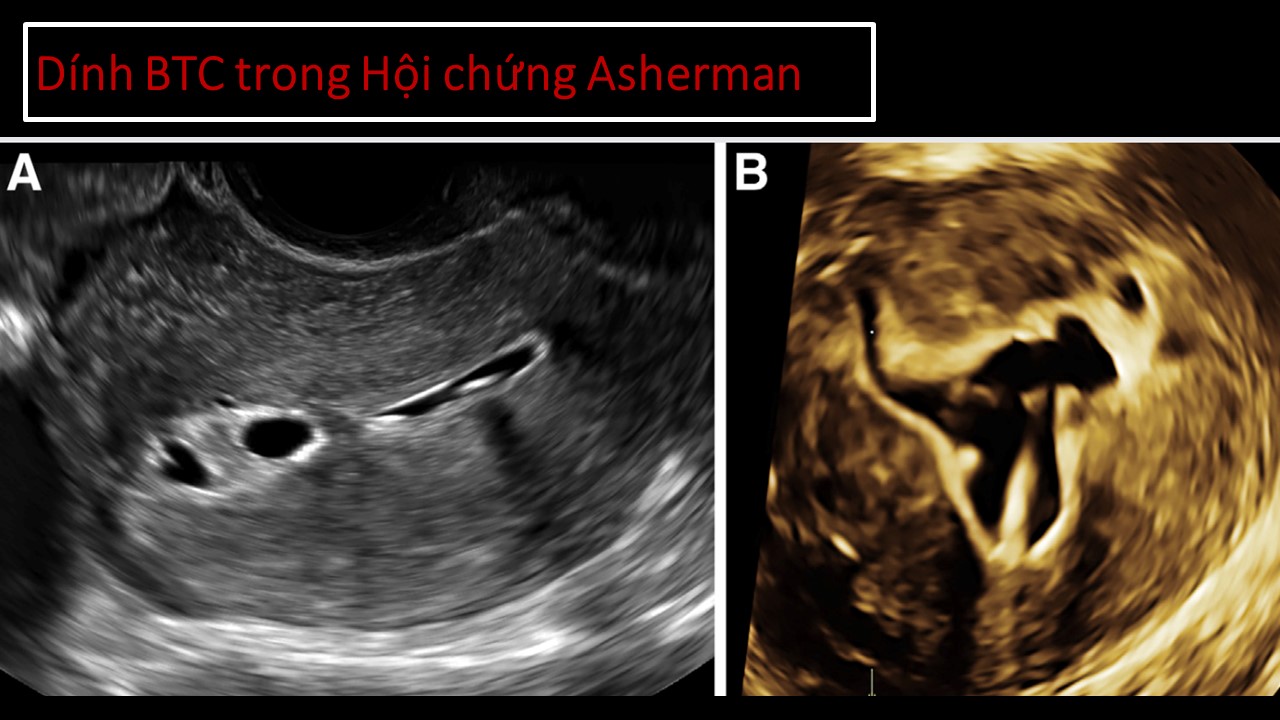

Vai trò của siêu âm trong chẩn đoán và điều trị hiếm muộn